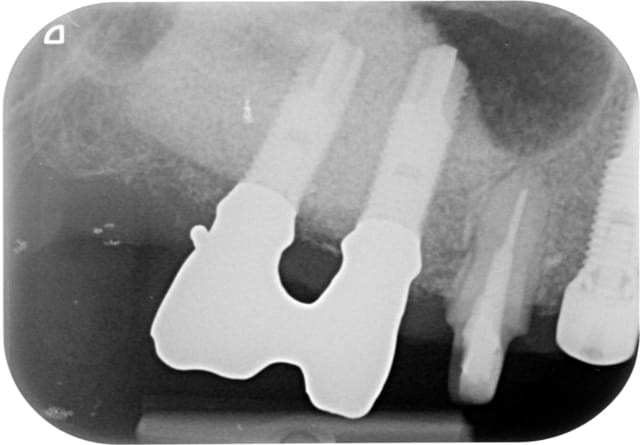

Tavéca

07/11/2014 à 09h40

la fin.

K  6 novembre 2014 lfkxbg - Eugenol

L  6 novembre 2014 gcsqeq - Eugenol

M  6 novembre 2014 gc5q3z - Eugenol

P  6 novembre 2014 cy54gy - Eugenol

Q  6 novembre 2014 vtispk - Eugenol

R  6 novembre 2014 nrhlqf - Eugenol